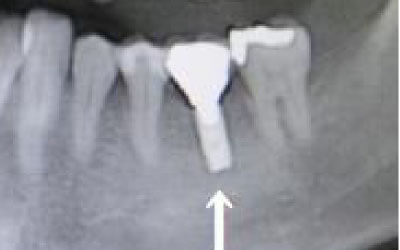

CTでは、骨や歯の状態を3Dで確認でき、正確な距離の測定も行えます。

骨の厚さや傾き、神経の位置などを事前にしっかりと測定することで、安全にインプラントを行うことができます。

2 神経を傷つけるリスク

インプラント治療では、顎の骨内を通る神経を傷つけるリスクがあります。

ただし、事前にCTで三次元的に神経との距離を測り、治療計画を慎重に立てれば、心配することはありません。

また、当院では過剰に削らないようにするためのストッパーも使用しています。